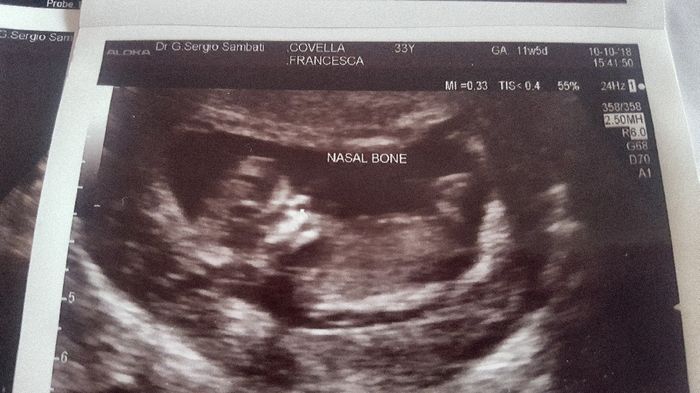

Buongiorno mammine.... vi presento il mio fagottino oggi ho saputo che è maschio ve lo ho evidenziato in giallo... Non so xke ma nn mi sembra che è maschio mi sento una femminuccia... mi sembra che in questa eco fosse un piedino voi ch3 ne pensate... secondo voi è maschio

Patti è a me? Io non ho saputo nulla dalla tn..qui ero a 11+6